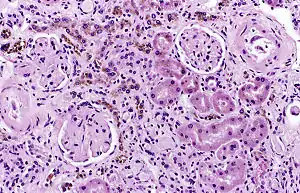

It is only found within cells (as opposed to circulating in blood) and appears to be a complex of ferritin, denatured ferritin and other material.[4][5] The iron within deposits of hemosiderin is very poorly available to supply iron when needed. Hemosiderin can be identified histologically with Perls' Prussian blue stain; iron in hemosiderin turns blue to black when exposed to potassium ferrocyanide.[6] In normal animals, hemosiderin deposits are small and commonly inapparent without special stains. Excessive accumulation of hemosiderin is usually detected within cells of the mononuclear phagocyte system (MPS) or occasionally within epithelial cells of the liver and kidney.

Hemosiderin often forms after bleeding (haemorrhage).[7] When blood leaves a ruptured blood vessel, the red blood cell dies, and the hemoglobin of the cell is released into the extracellular space. Phagocytic cells (of the mononuclear phagocyte system) called macrophages engulf (phagocytose) the hemoglobin to degrade it, producing hemosiderin and biliverdin. Excessive systemic accumulations of hemosiderin may occur in macrophages in the liver, lungs, spleen, kidneys, lymph nodes, and bone marrow. These accumulations may be caused by excessive red blood cell destruction (haemolysis), excessive iron uptake/hyperferraemia, or decreased iron utilization (e.g., anaemia of copper toxicity) uptake hypoferraemia (which often leads to iron deficiency anemia).

Cellular iron is found as either ferritin or hemosiderin. It is identified in cells by the Perls or Prussian blue reaction, in which ionic iron reacts with acid ferrocyanide to impart a blue color.<Wintrobe's Clinical Hematology>